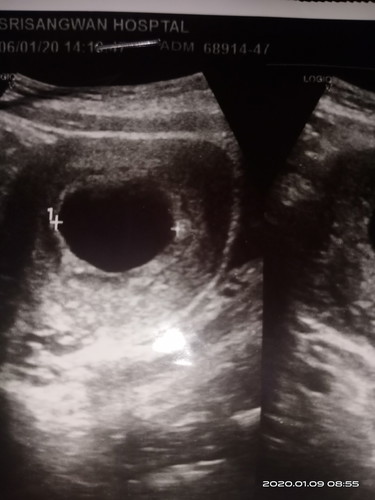

8 Wแล้วแต่ทำไมยังไม่เจอน้องละค่ะ ?

8W แล้วแต่ไม่เจอน้อง หมอนัดอีก2สัปดาห์ไปซาวอีกรอบ ตอนนี้เครียดมากๆ ?

คุนแม่ใจเยนๆน้ะค้ะ บ้านนี้ซาวด์ครั้งแรกตอน7วีค แทบใม่เหนน้องเมิลกันค้ะ หมอนัดซาวด์อีกที่2อาทิดถัดใป ตอน9วีค เหนน้องชัดขึ้นค้ะ คุนแม่อย่าเพิ่งคิดมากน้ะค้ะ